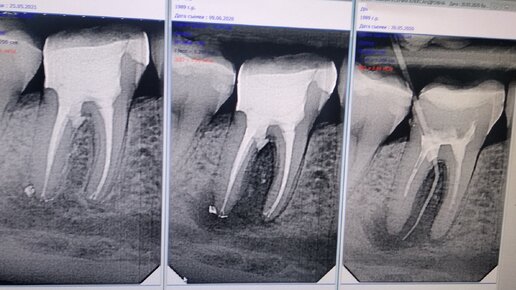

Знаю-знаю, статья вообще не в тему канала, но, год назад, когда вся эта история началась, я обещала поделиться результатами. Надеюсь, что те, кому обещала, ещё здесь. Небольшая предыстория: год назад мне диагностировали межкорневую кисту 46 зуба. На десне был свищ. Всё, что предложили мне и в государственной поликлинике, и в частных, в том числе, и в той пафосной стоматологии, где зубные щётки по 500 рублей продают - это удаление. Я отказалась, и решила лечить. При этом, я даже не знала и в душе не представляла, как эту кисту можно лечить, не знала, возьмётся ли за это вообще кто-то...